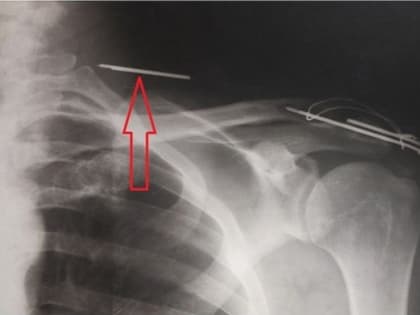

Врачи воронежской поликлиники вытащили пациенту спицу из шеи

Фото предоставлено пресс-службой Минздрава Воронежской области Медики из воронежской городской поликлиники №10 провели в одном из её помещений операцию.